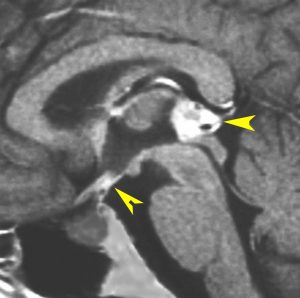

軽度の複視のみで発症した20代前半男性です。右上のように松果体腫瘍の前に割れ目が入るように第3脳室があり,両側視床に浸潤するために軽度の視床浮腫があり,ガドリニウムで強く増強され一部にのう胞があります。これだけでもgeriminomaにかなり特有の所見です。さらに,灰白隆起(矢印)のところに小さな神経下垂体germinoma腫瘍があります (bifocal tumor)。HCGは測定限界以下,AFP 2.5で,水頭症はありません。全ての臨床所見がgerminomaであることを示しています。

生検病理診断をしないでICE化学療法を1コース終えた後の画像です。腫瘍は消失しています。これでgerminomaであることが確認できたので,ICE化学療法を2コース追加して,25.2グレイの全脳室照射をして治療を終了しました。